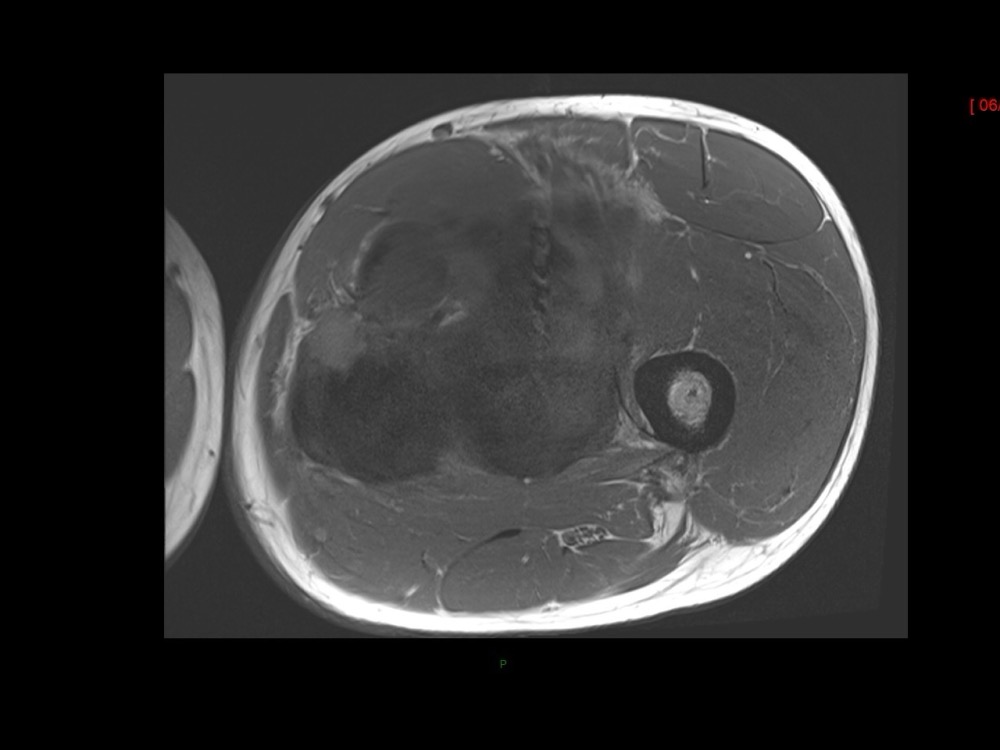

Moalla / Mihoubi-Bouvier / Drapé 18/05/2022